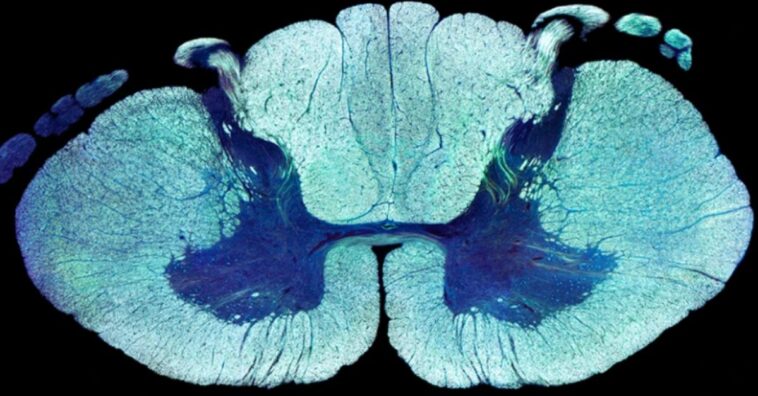

Em seguida, os pesquisadores mediram a atividade genética em milhares de neurônios individuais em amostras de tecido espinhal de camundongo. Isso produziu um mapa primorosamente detalhado dos tipos de células nervosas na medula espinhal inferior.

Eles então usaram um algoritmo de aprendizado de máquina para procurar neurônios de camundongos que mostravam mudanças na atividade genética em estágios definidos de reabilitação assistida por EES que se assemelhavam às mudanças observadas na capacidade de caminhar dos participantes humanos.

O algoritmo identificou uma subpopulação de interneurônios excitatórios – células nervosas que conectam neurônios motores e sensoriais – que pareciam se encaixar.